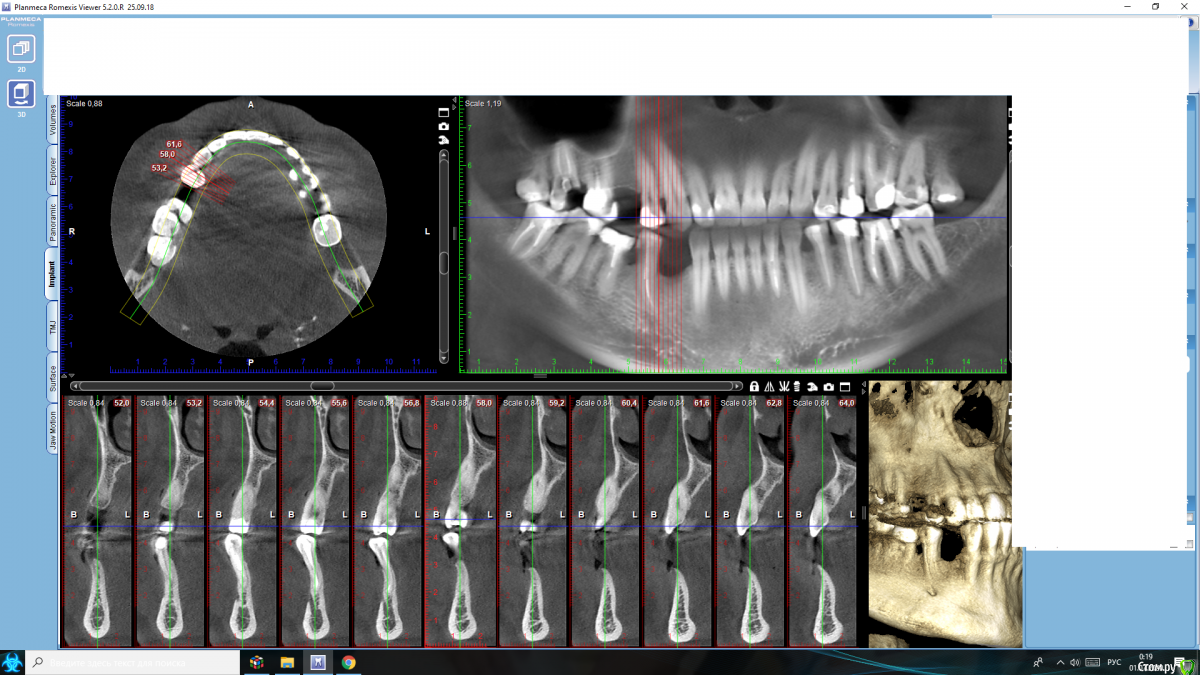

Nazim_NV86 Опубликовано 30 июня, 2020 Поделиться Опубликовано 30 июня, 2020 (изменено) Что сделать с правым низом ? Подкину вам пищу для размышлений.45 оголён прилично. -+3мм. Урбанизировать не возьмусь. До просмотра КЛКТ была мысль удалить его и "ламинировать" область 44,45 по пикам. Теперь что-то жалко стало. "база" не широкая. Изменено 30 июня, 2020 пользователем Nazim_NV86 Ссылка на комментарий

Nazim_NV86 Опубликовано 4 июля, 2020 Автор Поделиться Опубликовано 4 июля, 2020 Я бы 4.5 убрал, нкр по ширине и через 6 мес 2 имплменя смущает толщина базальной части и острый ножевидный гребень. Боюсь сосидж не даст нормальной ширины, а высоту даже можно потерять 1-1.5мм. Каркасными птфе не пользуюсь, мне там проще ламину(-ы) прибить. Ссылка на комментарий

Александр07 Опубликовано 8 июля, 2020 Поделиться Опубликовано 8 июля, 2020 меня смущает толщина базальной части и острый ножевидный гребень. Боюсь сосидж не даст нормальной ширины, а высоту даже можно потерять 1-1.5мм. Каркасными птфе не пользуюсь, мне там проще ламину(-ы) прибить. Ортодонтия интересный вариант, если не не рассматривать то сосидж с биогайдом наверно самый безопасный вариант, высота хорошая если даже потеряете немного то не страшно , думаю надо побольше ауто и перфорировать кортикалку хорошо , Вот похожий случай , но по срезам в основании пошире 1 Ссылка на комментарий